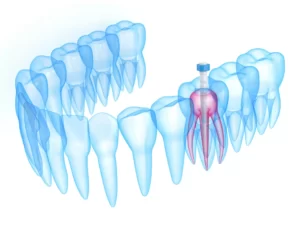

Kök kanal tedavisi; dişin en iç kısmında bulunan, dişin canlılığını ve beslenmesini sağlayan damar-sinir paketinin (pulpa) zarar gördüğü, yenilenemez duruma geldiği, canlılığını kaybettiği (nekroz) durumlarda uygulanır.

Endodontik tedavi, iltihaplı ya da ölü diş pulpasının kök kanallarından çıkartılıp, kanalların şekillendirilip, steril edilerek, bu boşluğun biyouyumlu kanal dolgu maddeleri ile doldurulması işlemidir.

Dişlerde madde kaybının fazla olduğu durumlarda, dişe kanal tedavisi uygulanmasının ardından kökün içine ‘post core’ materyali yerleştirilerek uygulanan tedavi yöntemidir. Bu sayede hem kökten hem de dişin üst kısmından destek alınarak dişin dayanıklılığı arttırılır.